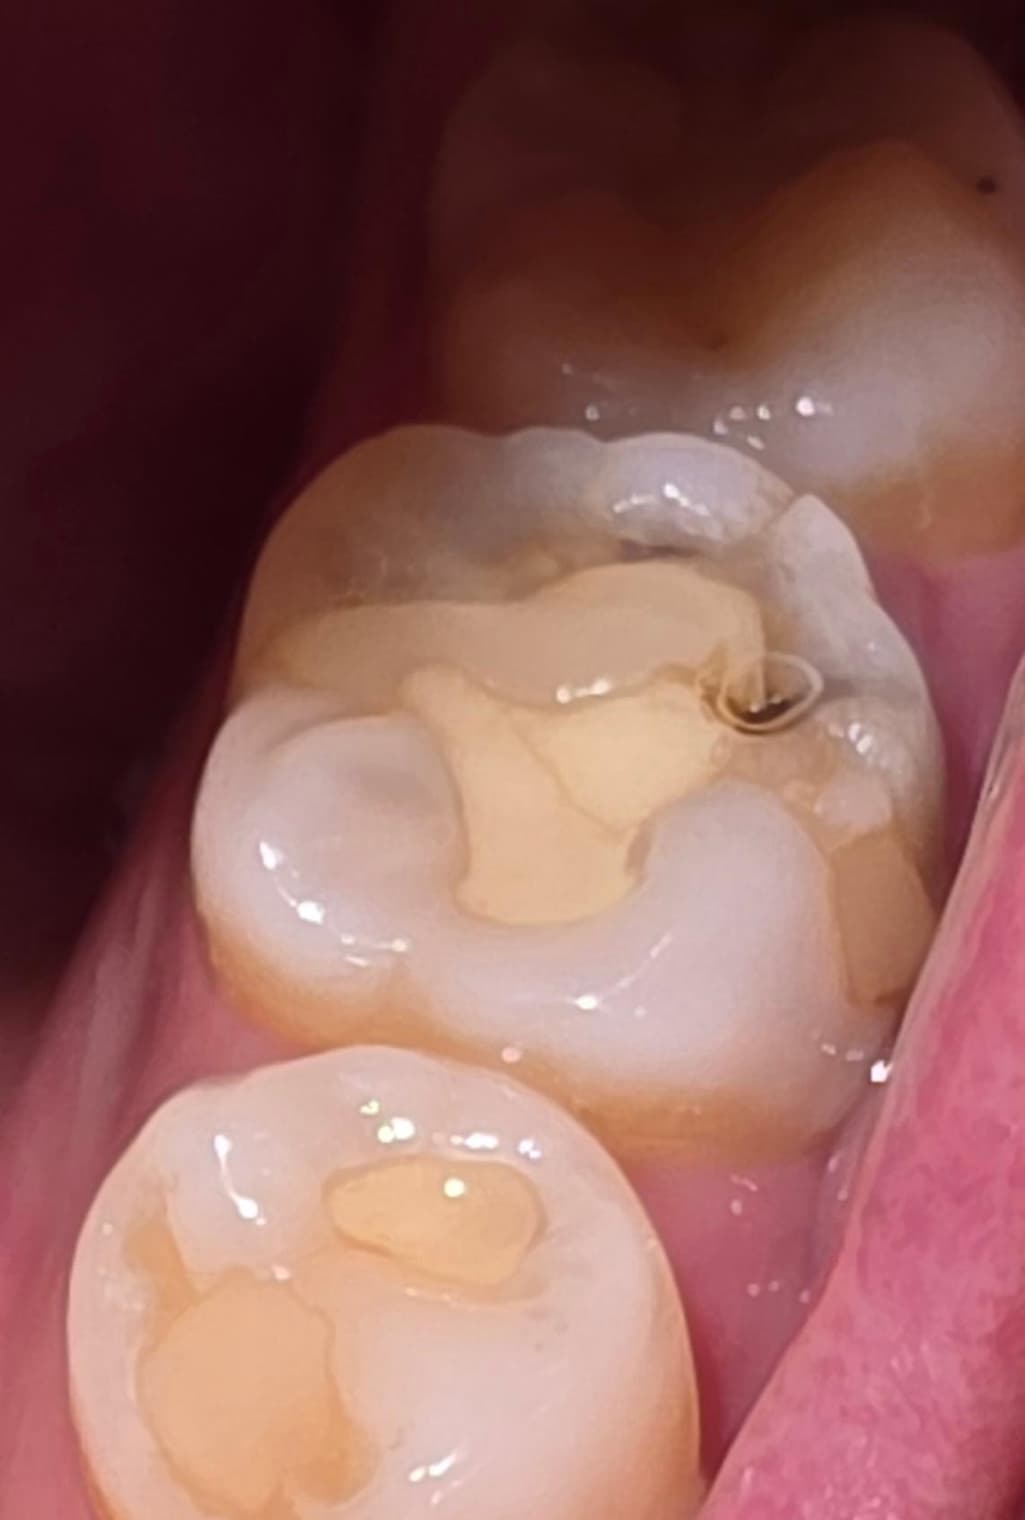

육포를 씹다가 갑자기 왼쪽 아랫부분 어금니가 욱신거리고 너무 아파서 카메라로 보니까 때운 부분이 저렇게 되어있던데 혹시 치아에 금이 간 건가요? ㅠㅠ

떼운부위가 깨져보이고 안쪽으로 충치가 생겼을수도 있고 치아에 금이 갔을수도 있으니 치과에 내원하여 확인하면 좋을것같습니다. 빠른 회복 바라겠습니다. 건강하세요.

떼운 부위가 깨져나갔네요, 사진상으로 봐서 명확하진 않으나 깨져나간 부위 외에도 금이 간 것처럼 보이기도 합니다. 치과 가보시기 바랍니다.

사진으로 봤을 경우에는 이전에 치과용 재료로 충전한 부분 주변에 충치가 생기면서 깨진 것으로 보입니다. 이런 경우 충치치료가 필요할 수 있습니다.

자세한 확인을 위해서 치과에서 진료를 받아보는 것을 권유드립니다.